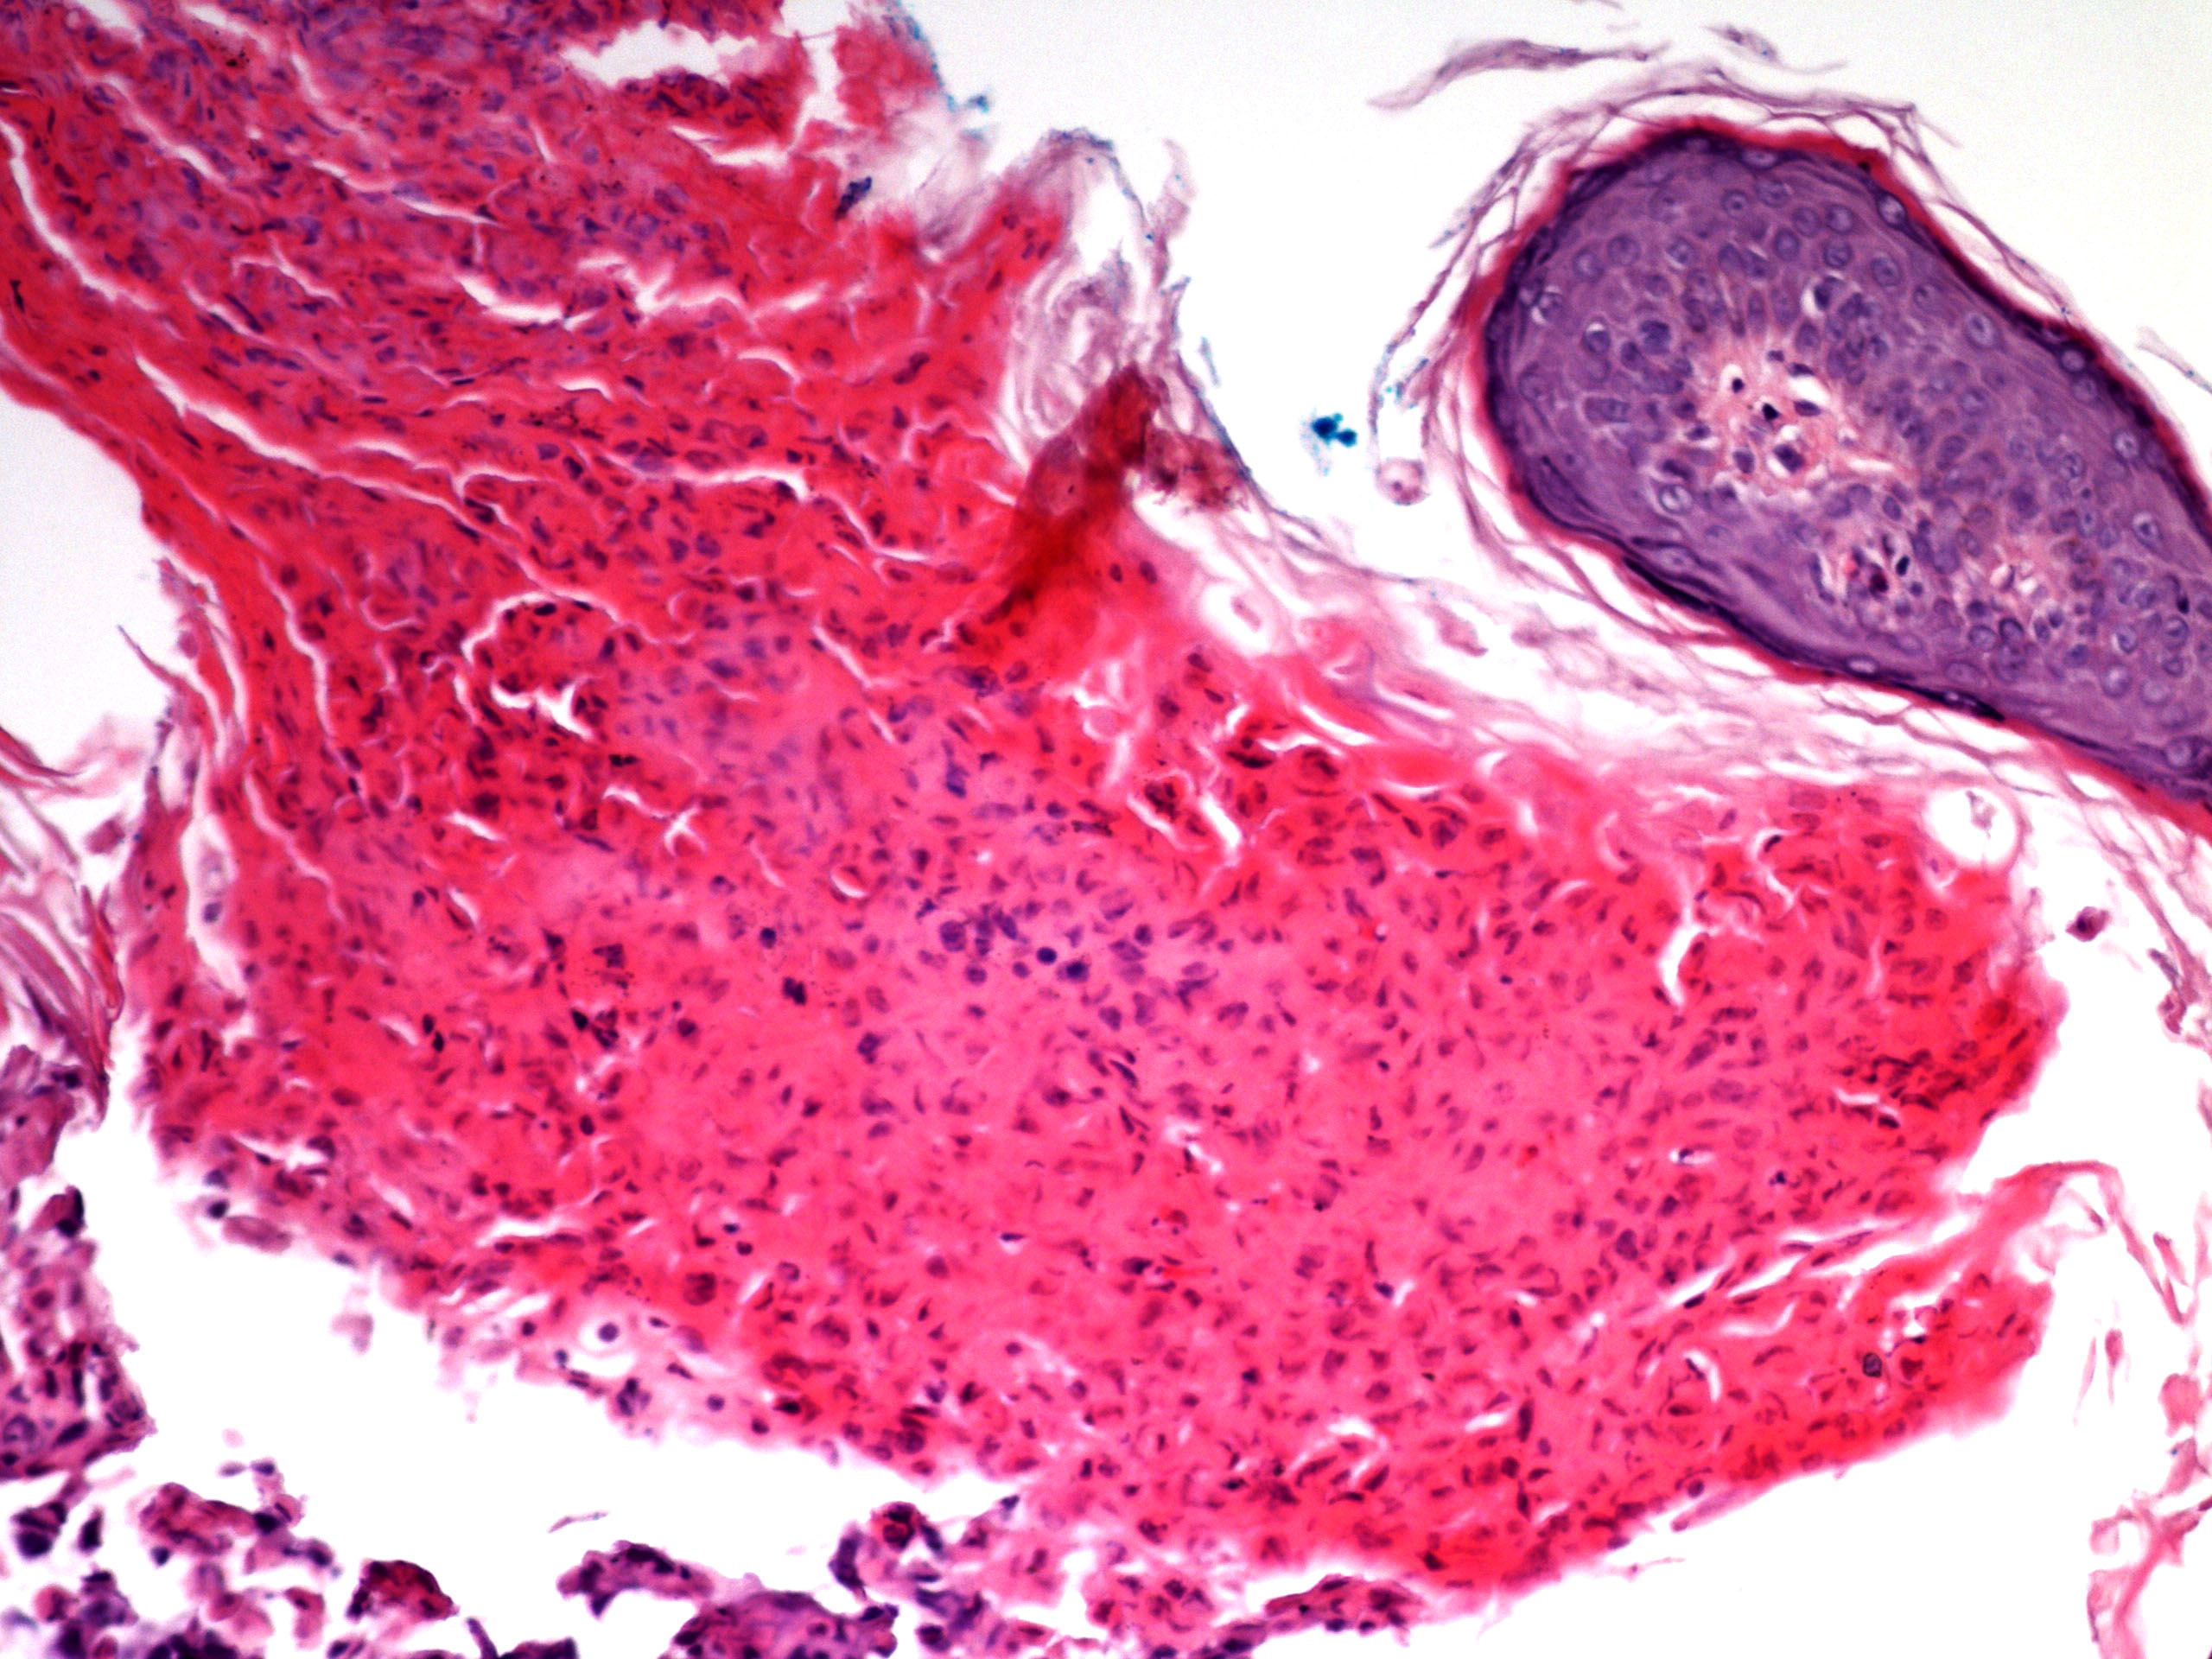

Microscopic (histologic) description

- Parakeratosis

- Variable epidermal thickness

- Acantholysis with characteristic dyskeratosis forming corp ronds and grains

- Corp rond: rounded keratinocyte in superficial spiny and granular layer with basophilic / pyknotic nucleus, perinuclear halo and often a rim of eosinophilic cytoplasm (J Dermatol 2017;44:232)

- Grain: elongated keratinocyte in the stratum corneum with small basophilic nuclei and intensely pink cytoplasm; appears as plump parakeratosis; may form tiers (J Dermatol 2017;44:232)

- Corp rond and grain type dyskeratosis is classical but not specific for Darier disease (see Differential diagnosis)

- Suprabasal acantholysis and clefting with retained single layer of basal keratinocytes overlying dermal papillae which appear to project into the acantholytic cavity (villi) (J Dermatol 2016;43:275)

- Frank bullae may occur in cases with extensive acantholysis and large clefts (Arch Dermatol 1982;118:278)

- Superimposed fungal, bacterial and herpetic infections may be seen (J Eur Acad Dermatol Venereol 2013;27:1405, Am J Dermatopathol 2017;39:370, Dermatol Ther 2020;33:e14500, Br J Dermatol 2015;172:837, Acta Derm Venereol 2017;97:139)

- Variable mild perivascular inflammatory cell infiltrate

- Variants: extensive pseudoepitheliomatous hyperplasia, comedonal lesions with prominent villus formation and hemorrhagic bullous lesions (Am J Dermatopathol 2015;37:323, J Dermatol 2006;33:477, J Cutan Med Surg 2016;20:478)

Microscopic (histologic) images

- Comment: The specimen exhibits parakeratosis, epidermal hyperplasia, acantholytic dyskeratosis with prominent corp rond and grain formation, suprabasal clefting with formation of villi and a mild superficial perivascular lymphocytic infiltrate. Although similar acantholytic dyskeratosis may be seen in a number of entities, given the clinical history of greasy papules in a seborrheic distribution, a positive family history and persistence of lesions, the findings are most consistent with Darier disease.

A. Darier disease. The photomicrograph shows acantholysis with dyskeratosis (corp ronds and grains) as well as the formation of villi classically seen in Darier disease. While Hailey-Hailey disease may have acantholysis with dyskeratosis, prominent corp ronds and grains are lacking. Pemphigus has bland acantholysis and herpes simplex shows distinct viral cytopathic change. Seborrheic dermatitis is a spongiotic dermatitis.